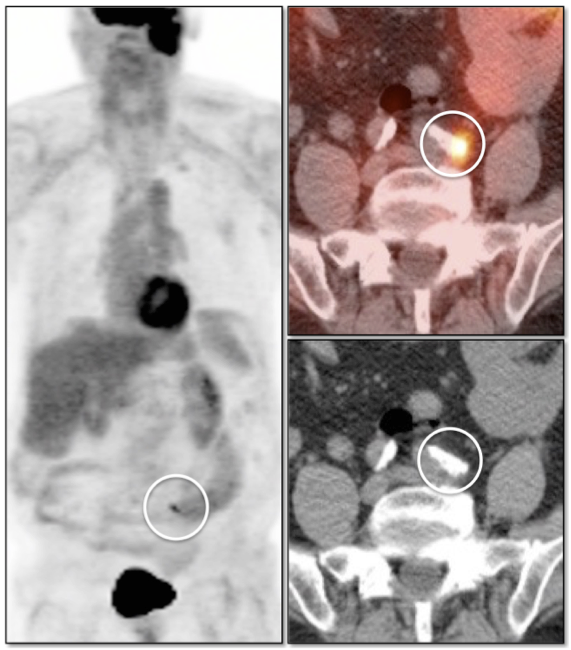

Lung Nodule Identification:

NAC images can occasionally be useful in identifying mild to moderately FDG-avid lung nodules, especially those located in the lung periphery or lung bases.